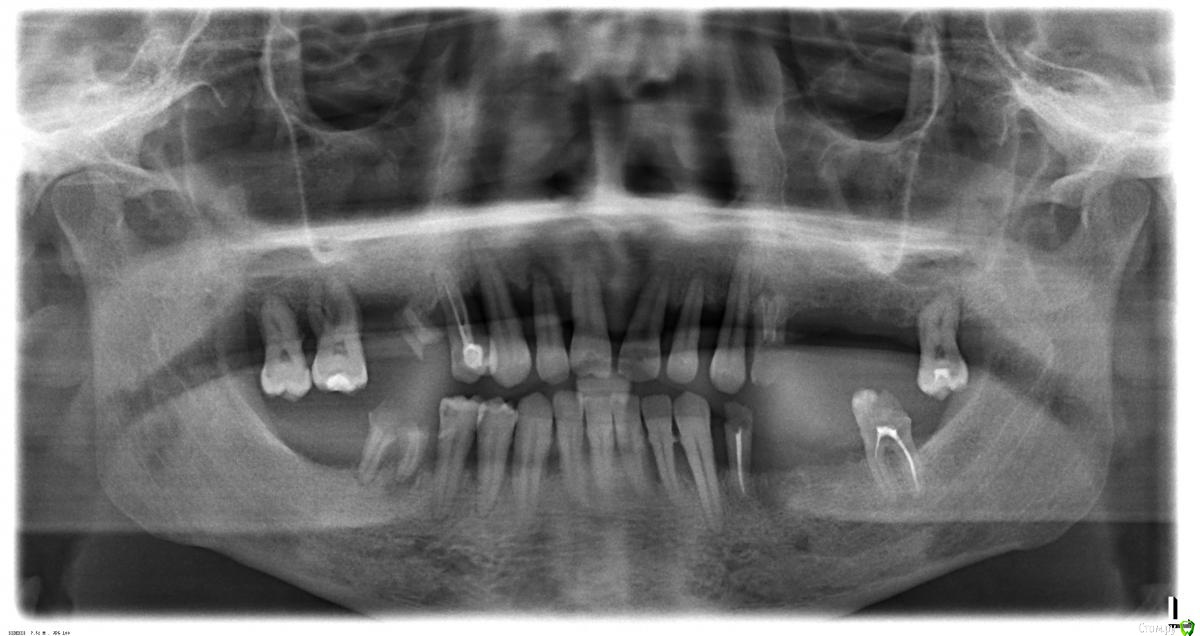

Пациент1 Опубликовано 24 марта, 2018 Поделиться Опубликовано 24 марта, 2018 Всем привет.Есть значительная подвижность верхних зубов, подскажите пожалуйста, какие возможны варианты в данном случае? Ссылка на комментарий

Пациент1 Опубликовано 25 марта, 2018 Автор Поделиться Опубликовано 25 марта, 2018 Суть вопроса - выбор оптимального варианта, нужно зубы сделать.1. Имплантация с одномоментной нагрузкой(за 1 неделю) или классическая(удалить-пауза несколько месяцев-имплантация-пауза несколько месяцев-протезирование)?2. Центральная зубы снизу оставить, по краям два моста, каждый на двух имплантах?3. Марка имплантов с хорошей приживаемостью?4. Необходимость синус-лифтингов сверху? Ссылка на комментарий

Irouil Опубликовано 28 марта, 2018 Поделиться Опубликовано 28 марта, 2018 (изменено) Это слишком общие вопросы. Чтобы говорить о возможности имплантации вообще надо бы КТ смотреть. Одномоментная имплантация сокращает сроки реабилитации, помогает сохранить поддерживающие имплантат ткани для надёжности долгосрочных прогнозов на протезирование (в сочетании с другими методами консервации этих тканей), позволяет получить несъёмные протезы с первых дней после удаления зубов (в большинстве случаев). Преимущества отсроченной имплантации в основном состоят в простоте ее выполнения с технической точки зрения, что повышает ее предсказуемость. Чтобы подробнее высказаться нужны бы фотографии во рту и та самая Компьютерная Томограмма о которой я писал выше Изменено 28 марта, 2018 пользователем Irouil 1 Ссылка на комментарий

Пациент1 Опубликовано 5 апреля, 2018 Автор Поделиться Опубликовано 5 апреля, 2018 КТ есть, а что значит сохранение поддерживающих имплантат тканей для надёжности долгосрочных прогнозов на протезирование?То что сразу зубы и сроки меньше это конечно существенные плюсы, но и минусы, в индивидуальных случаях, похоже тоже существенные, иначе бы на классическую имплантацию вообще бы не было желающих?То что не все доктора рекомендуют одномоментную имплантацию, это чаще всего из-за того что им неохота связываться с большими рисками в лечении при сложных случаях или все-таки при сложных случаях, некоторым категорически не подходит одномоментная имплантация?Плюс понятно что одномоментная имплантация выгоднее для доктора в плане дохода за более короткий срок, что возможно, тоже имеет дополнительный вес в чашу весов при рекомендациях в выборе лечения... Ссылка на комментарий